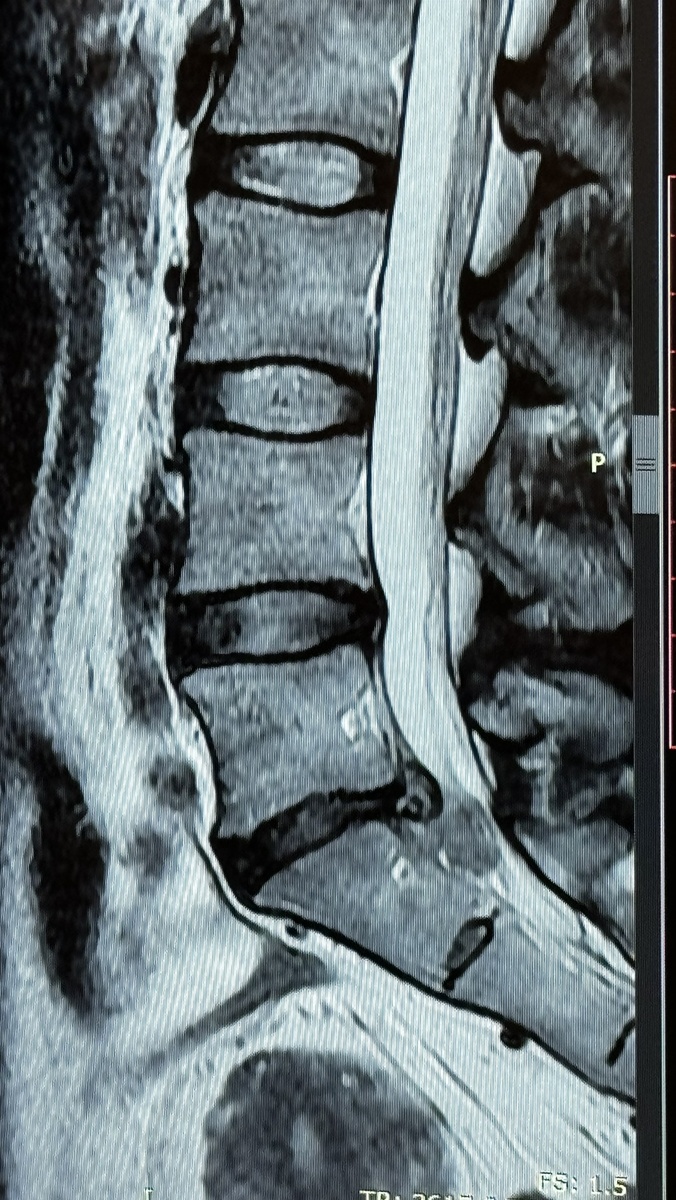

По возвращении я нахожу клинику физиотерапии и реабилитации. Они мне оформляют письмо в Бангкок Госпиталь, чтобы снизить стоимость МРТ. Без этого письма, стоимость диагностики 16000 батов(38400 рублей). Медицина в Таиланде очень дорогая! Поэтому, страховка – мастхэв. С письмом сумма выходит в два раза меньше. По результатам обследования, произошло секвестрирование(разрыв) той самой грыжи. Ее содержимое вышло в межпозвоночное пространство и дальше. Я сейчас могу привирать термины, описываю своими словами, уж простите. В общем, насколько я поняла, в момент вертикального давления массажистки произошла компрессия дисков и хлоп! грыжа вскрылась. Было сужено пространство и сильное давление на нервные корешки.

Дальше у меня была эпопея на пол года по восстановлению. Я прошла два курса лазера, направленного на резорбцию секвестра плюс иголки, плюс гимнастика в бассейне. Через пару недель после начала уже после окончания приема обезболов, боль начала спадать. Я по-прежнему хромала. Стопа не работала, икроножная тоже. Примерно через месяц стало получаться в воде подняться на мысок. На суше никак. Только месяцев через 8 работы на тренажерах я смогла оторвать пятку на пару сантиметров от пола. После того, как завершилась терапия, болей уже не было. Я сделала проверочное МРТ, которое подтвердило полное исчезновение грыжи(почти полное) и расширение пространства для нервов. Дальше работала уже сама.